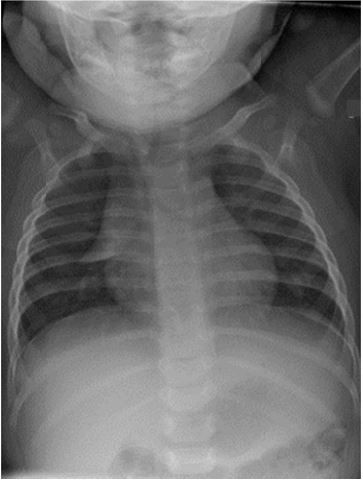

Menino, 6 meses, comparece ao pronto-socorro com história de febre, obstrução nasal, coriza, e tosse há 3 dias, e cansaço há um dia. Nega vômitos ou inapetência. Exame físico: bom estado geral, corado, hidratado, acianótico, dispneico, T=36,2 ºC, FC=163bpm, FR=71irpm, PA=80x45 mmHg, oximetria (ar ambiente) = 91%, pulsos cheios, enchimento capilar=2 segundos; Otocospia: membranas timpânicas translucidas e sem hiperemia; Pulmão: murmúrio vesicular diminuído à direita com raros sibilos bilateralmente; Coração: ritmo duplo regular sem sopros, bulhas normofonéticas. Radiograma de tórax: